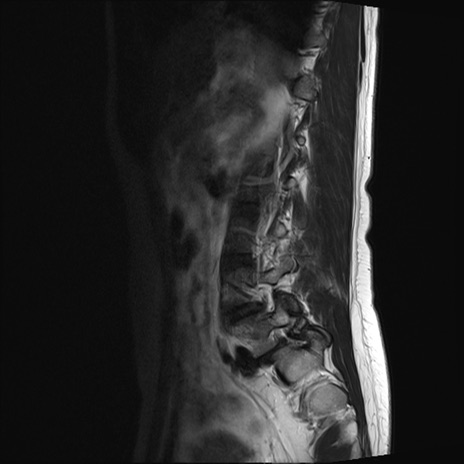

【整形】TIPS症例4 腰椎MRI T2WI(矢状断像)

腰椎MRI

STIR(矢状断像)

横断像と矢状断像